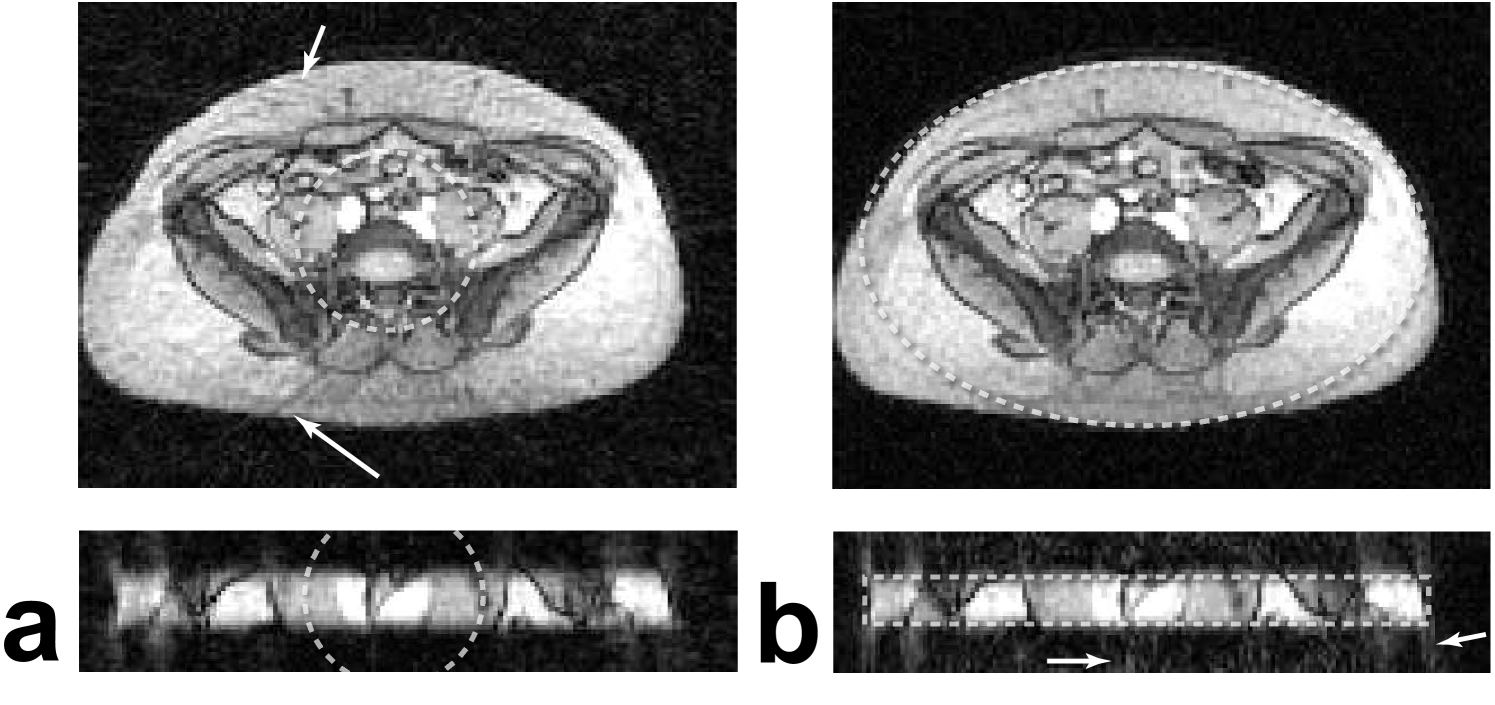

Figure 12: 2D PR Lower leg images with various FOV shapes, shown by the dashed lines. (a) 25 cm circular FOV requiring 393 projections, (b) 7.5 x 25 cm elliptical FOV requiring 197 projections, (c) 6.5 x 24 cm rectangular FOV requiring 195 projections, (d) 12.5 cm circular FOV requiring 196 projections. The non-circular FOV images (b,c) show no increase in aliasing artifacts or loss of resolution but were acquired with half the projections. The circular FOV acquired with half the projections (d) results in significant aliasing artifacts.

IV-C MRI Experiments

In vivo 2D PR leg images acquired with isotropic and anisotropic FOVs are shown in Fig. 12. The reduced FOV images (b-d) were acquired with half the number of projections as the full FOV image (a). The isotropic reduced FOV (d) results in significant streaking aliasing artifacts, while using anisotropic reduced FOVs tailored to the shape of the leg (b,c) results in no increase in artifact compared to the full isotropic FOV image. The images without aliasing (a-c) are all slightly undersampled, as shown by the overlaid FOV shapes, but no aliasing is visible due to the relatively diffuse aliasing pattern of PR.